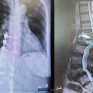

إنجاز طبي جديد في مستشفى العمران العام: نجاح عملية تثبيت داخلي معقدة لعظمة الزند

الواحة نيوز

8:21 م - 3 نوفمبر، 2025